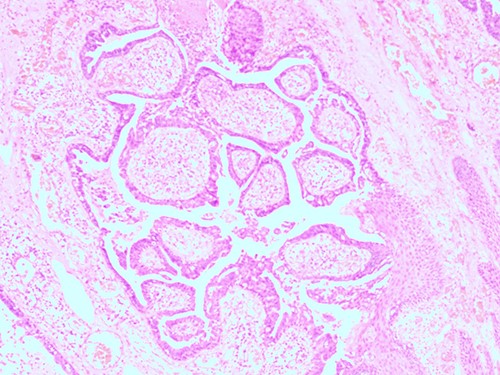

The histopathological examination found cystic invaginations of the infundibular epithelium projecting into the dermis, covered by a double cell layer (Fig. 2), proliferation of glands with prominent papillary architecture (Fig. 3) and fibrous cores containing numerous stromal plasma cells (Fig. 4). Other findings include verrucous (papillomatous) epidermal hyperplasia with hyperkeratosis and hypergranulosis (Fig. 5), irregular duct-like structures and cystic spaces (Fig. 6) and glands with double layer of cuboidal columnar epithelium and numerous stromal plasma cells (Fig. 7). These findings are compatible with Syringocystadenoma papilliferum with no signs of malignancy.

H&E staining 10× magnification. Proliferation of glands with prominent papillary architecture.